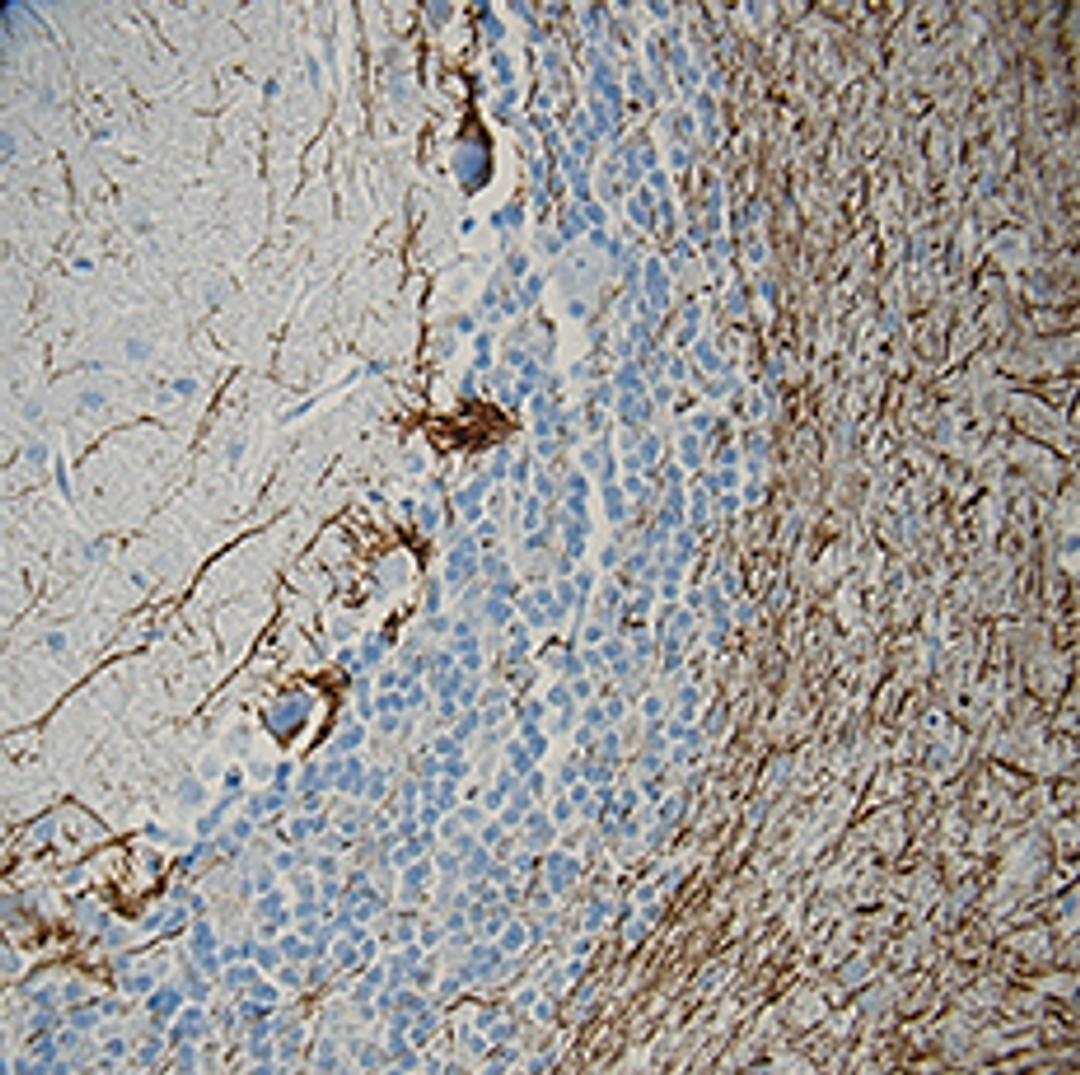

Purified anti-Neurofilament H (NF-H), Phosphorylated; Clone: SMI 31; Reactivity: Mammalian, Chicken, Xenopus; Apps: IHC, WB, ICC, ELISA; Size: 100 μl

- Immunohistochemistry (IHC)